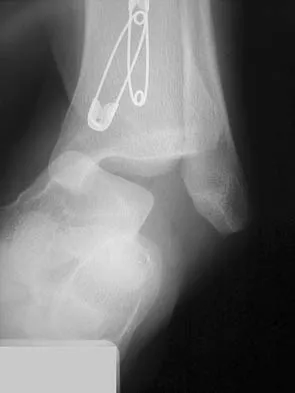

A 28-year-old professional dancer reports a 3-month history of progressive pain in the posterior aspect of the left ankle. Her symptoms are worse when she assumes the en pointe position. Examination reveals tenderness to palpation at the posterolateral aspect of the ankle posterior to the peroneal tendons which is made worse with passive plantar flexion. There is no nodularity, fluctuance, or tenderness of the Achilles tendon. The neurovascular examination is unremarkable. A lateral radiograph and MRI scan are shown in Figures 16a and 16b, respectively. Management should consist of

The imaging studies reveal findings typical of the os trigonum syndrome. This condition results from inflammation between the os trigonum and the adjacent talus. The symptoms of posterior ankle pain are exacerbated by plantar flexion, which stresses the fibrous union between these two bones. Definitive management of the high-level athlete involves excision of the os trigonum from a medial approach, although arthroscopic excision has also been described. The os trigonum is not an intra-articular structure; therefore, ankle arthroscopy is neither diagnostic nor therapeutic. Abramowitz Y, Wollstein R, Barzilay Y, et al: Outcome of resection of a symptomatic os trigonum. J Bone Joint Surg Am 2003;85:1051-1057. Mouhsine E, Crevoisier X, Leyvraz P, et al: Post-traumatic overload or acute syndrome of the os trigonum: A possible cause of posterior ankle impingement. Knee Surg Sports Traumatol Arthrosc 2004;12:250-253.